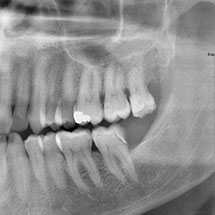

Panoramique dentaire

Il permet d’étudier la formule dentaire (nombre et position), la structure des dents et leur environnement (parodonte). Il permet de visualiser le fond des sinus (sinusite), et les articulations temporo mandibulaires (arthrose, déplacements).

On recherche surtout des lésions dentaires, des dents incluses, des kystes, des granulomes (infections), des anomalies osseuses ou des fractures.

Chez l’enfant, on analyse l’évolution de la dentition.